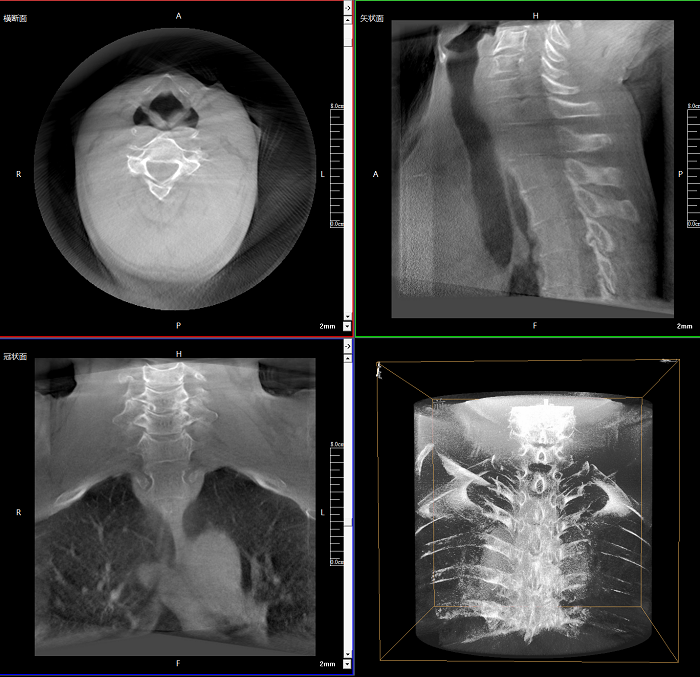

該設(shè)備可進(jìn)行快速的術(shù)中三維掃描,生成類(lèi)CT斷層圖像和立體3D圖像,保障植入物置入效果。廣泛適用于骨科、脊柱外科、矯形外科、創(chuàng)傷骨科等其他領(lǐng)域。

●極速成像僅需8秒,從數(shù)據(jù)采集結(jié)束到完成三維重建斷層影像